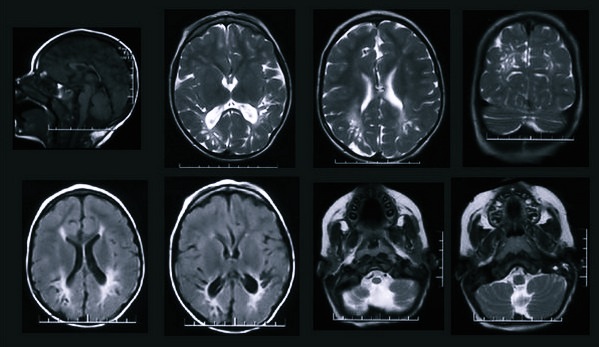

Вредно ли МРТ для здоровья человека, если сканируется мозг? Этот орган, как и любой другой, не следует облучать по любому поводу, хотя излучения сотовых вышек и беспроводного интернета находятся вокруг нас почти повсеместно.

Обследования мозга МРТ проводят только при наличии строгих показаний:

- постоянно болит голова;

- регулярные головокружения;

- подозрение на развитие опухоли в головном мозге;

- нарушение мозговой деятельности.

Так вредно ли делать МРТ головного мозга? Могут ли ткани при этом облучаться? Если это безопасно, то в каких случаях есть риск? Бывают ли осложнения? Рассмотрим особенности процедуры при исследовании мозга.

Пациента укладывают на особую площадку, которая непрерывно движется. На мозг при этом воздействует сильное электромагнитное поле. На аппаратуру подаются данные – реакция ядер водорода после мощного электромагнитного импульса. Как показали детальные исследования, никакого вреда ни мозгу, ни другим органам при этом не наносится. Польза от таких исследований в сотни раз выше, чем возможные риски. Никаких побочных явлений ждать не стоит. А вот эффект просто колоссальный. Можно в деталях и разных проекциях увидеть тело человека изнутри.